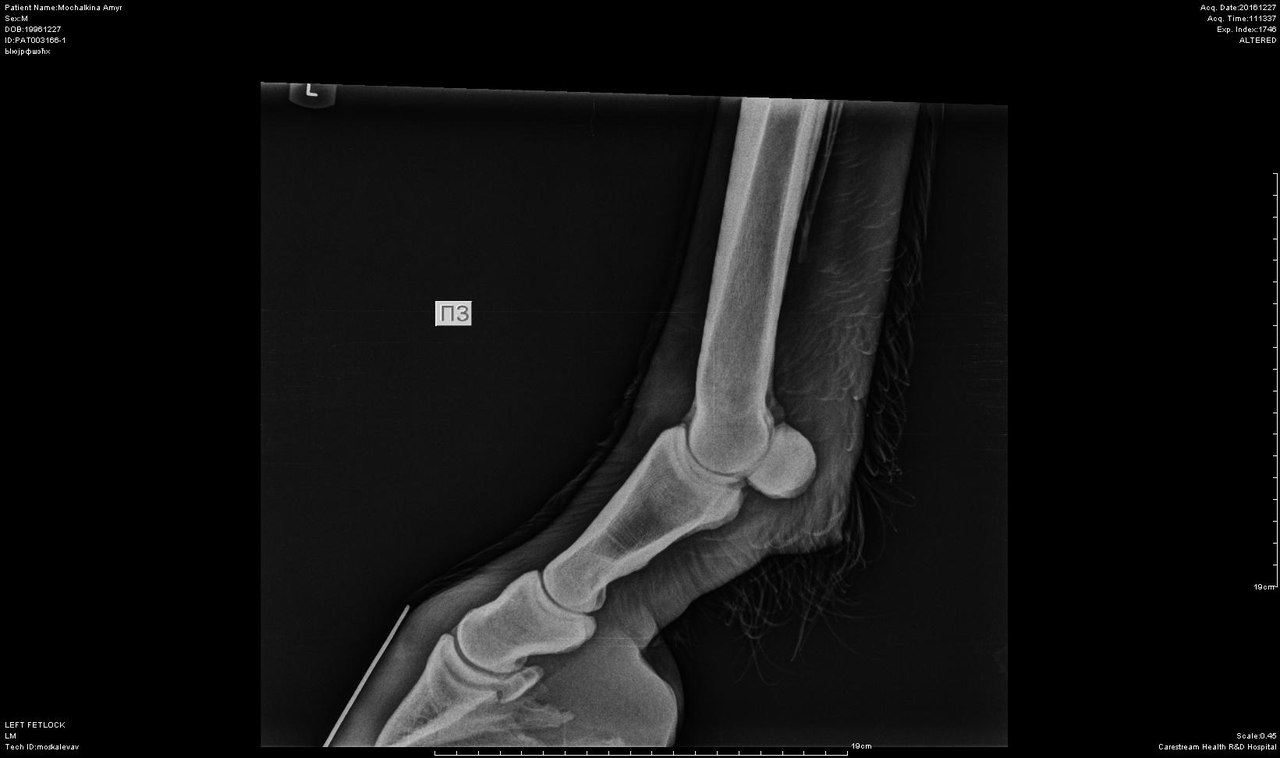

В анамнезе у коня остеоартроз правого скакательного сустава и левого путового на тазовой конечности (диагноз подтвержден рентгенологически в декабре 2016 г.), имеется выраженная хромота, никаких верховых нагрузок Амур не несет и нести не сможет.